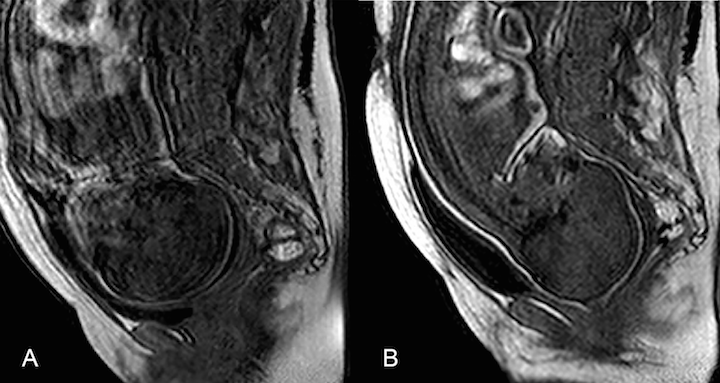

Les chercheurs ont observé par imagerie par résonance magnétique (IRM) le deuxième stade de l'accouchement par voie basse chez sept femmes. Ils ont ensuite réalisé des reconstructions tridimensionnelles du fœtus pour quantifier la déformation du crâne. Ils ont observé une déformation du crâne et du cerveau dans les sept cas, mais cette déformation n'était pas visible cliniquement après la naissance dans cinq cas. Cela pourrait dépendre du degré d'élasticité des os du crâne.

Les deux figures suivantes montrent la déformation du crâne avant (violet) et pendant (rouge) l'accouchement.